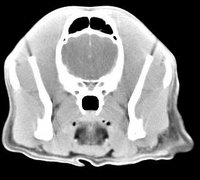

imágenes de TC en el perro | ||||||||||

ejemplo de imágenes de TC en el perro. Nótese la celulitis en la región parotídea izquierda | ||||||||||